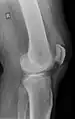

X-ray of a tear of the patellar tendon. On the left: The kneecap is pulled up. On the right: Significant dent in the soft tissue above the kneecap.